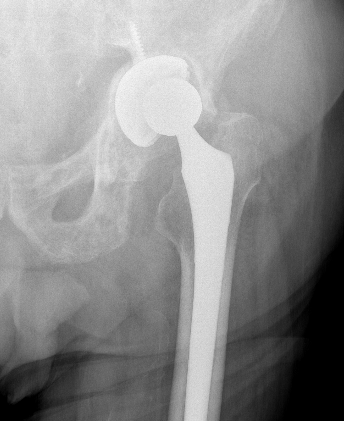

Revision THA for instability

Options

Liner exchange / augmentation liner

Acetabulum revision - reposition

Femoral revision - offset, LLD, anteversion

Constrained liner

Dual mobility